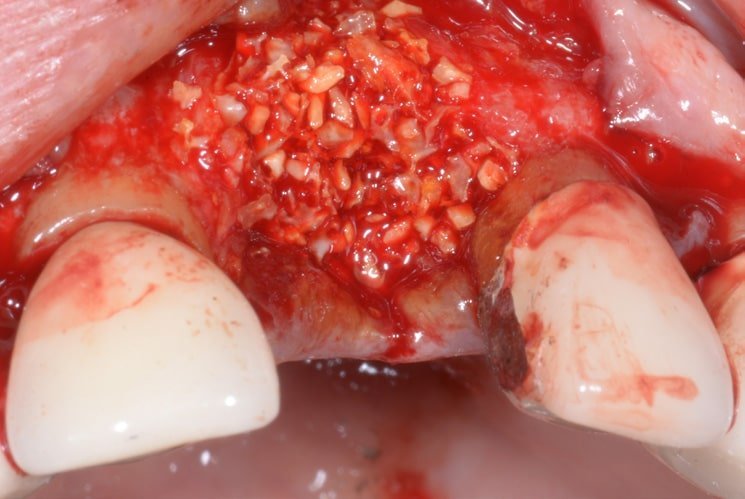

Since the implant has no vestibular bone, it was decided to insert some bone regeneration material and cover everything with a T-barrier collagen membrane for better healing and maintenance of the tissues.